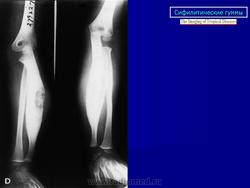

Гуммозный (очагово-деструктивный процесс) при раннем врожденном сифилисе наблюдается не часто. Локализуется преимущественно в локтевой и большеберцовой костях, а также в плоских костях. Изменения могут наблюдаться в метафизе, в диафизе, располагаются поднадкостнично и в костном мозгу. Изменения могут быть одиночными и множественными. Диаметр их 0,2 до 0,8 см. На рентгенограммах - изолированные очаги деструкции имеют овальную или округлую форму, окружены зоной остеосклероза.

Диффузный сифилитический остеопериостит при позднем врожденном сифилисе по частоте поражения занимает 1 место. Поражается преимущественно большеберцовая кость. На рентгенограммах утолщенная окостеневшая надкостница сливается с корковым слоем. Во всех слоях кости - массивный склероз, кость на большом протяжении теряет свою структуру. Наружный контур четкий, но может быть несколько волнистым. Среди склероза могут наблюдаться очажки деструкции за счет миллиарных гумм - это сочетание множественного гуммозного и диффузного сифилитического периостита.

Сифилитические остеомиелиты. Множественный гуммозный остит при расположении гумм на различной глубине имеет характер гуммозного остеомиелита, наиболее часто локализуется в диафизе. Процессы, локализующиеся в диафизе, метафизе или эпифизе, имеют свои особенности. Сифилитический процесс в диафизе сопровождается бурной эндостальной реакцией, вокруг гумм наблюдается массивный реактивный склероз. Гуммозный процесс в метафизе имеет некоторые черты диафизарного, однако эндостальная и периостальная реакция выражены слабее. Процесс не переходит в эпифиз через ростковый хрящ. Сифилитические эпифизиты протекают в форме единичных гумм. При позднем врожденном сифилисе встречаются редко. Определяется очаг деструкции со слабо выраженным склерозом и небольшим периоститом.

Раньше работала в больнице, где было отделение по выхаживанию новорожденных. Очень часто встречалась с врожденным сифилисом, которого с каждым годом становится все больше и больше. Основными проявлениями были остеохондрит и сифилитический периостит. Вот несколько снимочков с этой патологией, быть может, кто-то не встречался с ней.